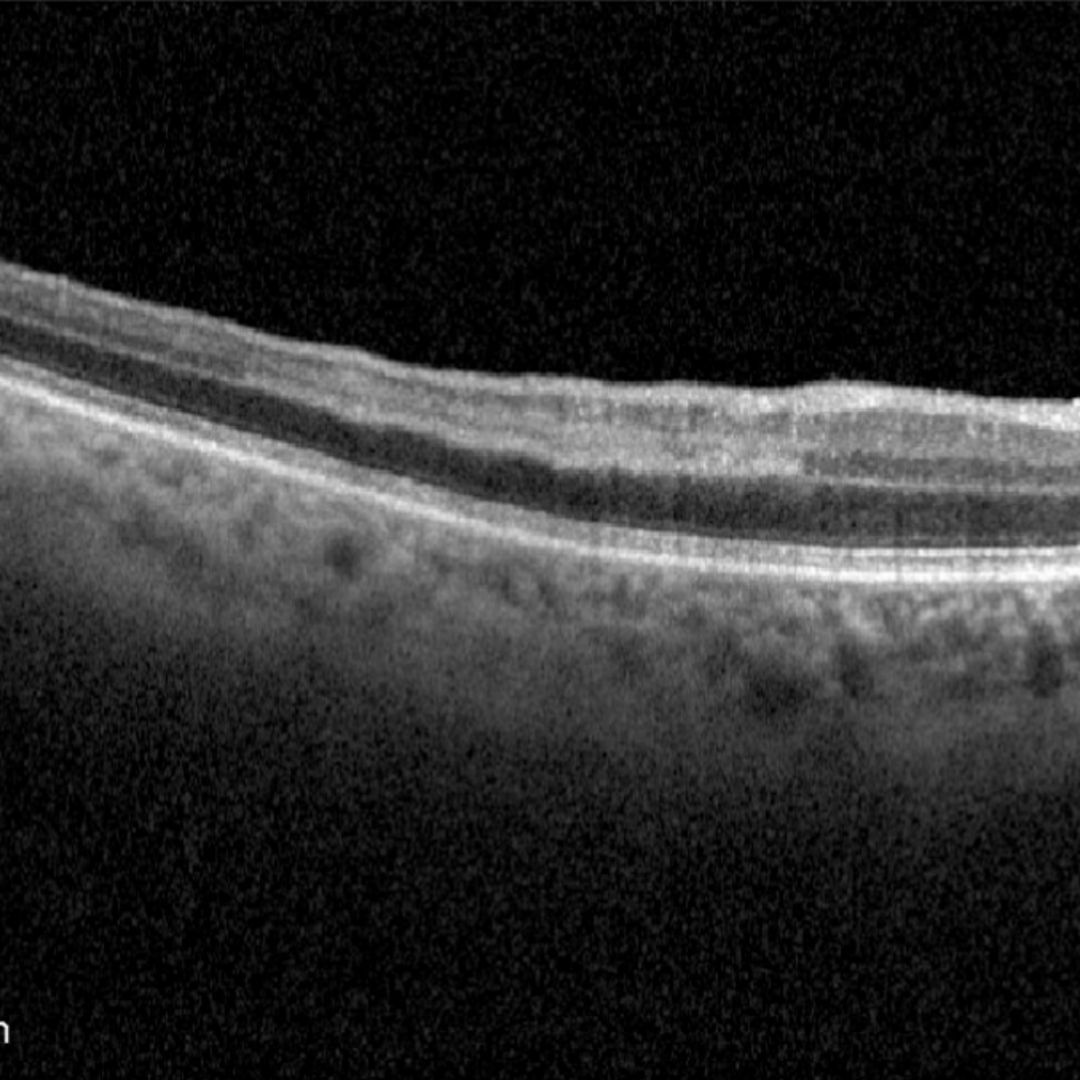

PAMM is an OCT-based clinical sign characterised by the presence of a hyper-reflective band within the inner nuclear layer (INL) of the retina which, over time, results in thinning of the INL without involvement of the outer retina. This finding is typically associated with a paracentral visual field defect and a hypo-reflective paracentral lesion on infra-red imaging.